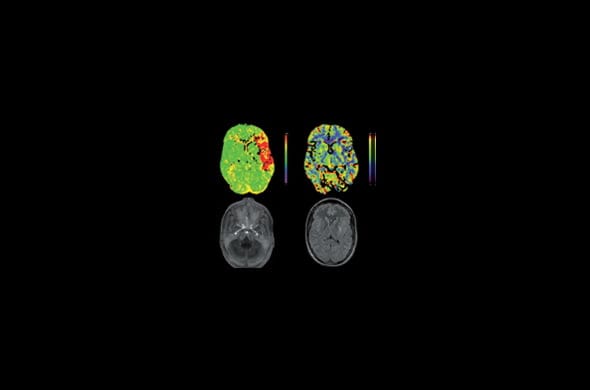

Por eso mismo, no es baladí destacar la importancia de un diagnóstico precoz, a la par que efectivo. Entre los métodos más utilizados en la actualidad aparecen el TAC (tomografía axial computarizada), que detecta sangrados de tipo agudo, como los que se instauran en menos de 24h. También son muy importantes la RMN (resonancia magnética), muy importante a la hora de delimitar con suma exactitud la anatomía cerebral, o la angiografía, capaz de delimitar el árbol vascular de manera precisa.